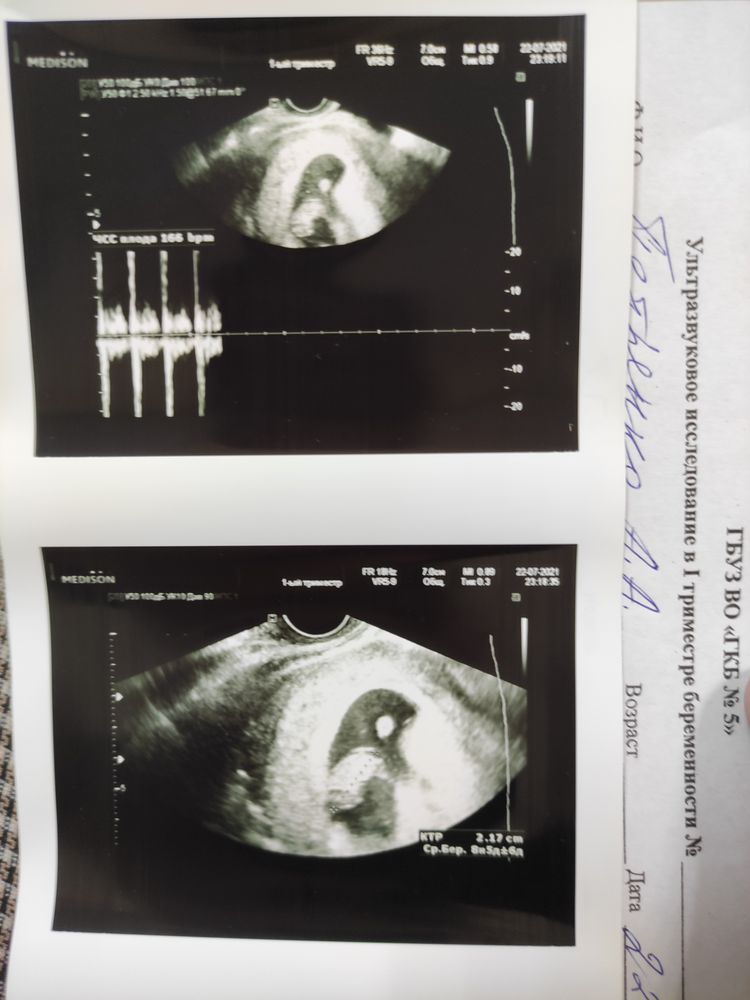

Анна, да, все верно, если учитывать действие лекарства, которое могло выступать тератогеном, то обычно к моменту первого скрининга все более или менее ясно. Изображение